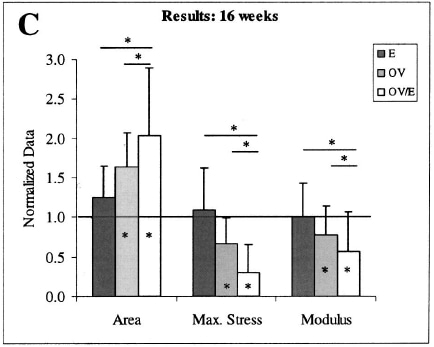

4. Комбинацията от натоварване на натиск и натоварване на опън е по-вредна от всяко от двете самостоятелно. Проучване на Soslowsky et al. (2002) сравняват 3 групи мишки помежду им: В една група манипулираха акромиалната арка, за да симулират външна компресия, една група имаше по-високи натоварвания на опън, тъй като трябваше да бяга на бягаща пътека повече от другите групи, и комбинирана група. Те установяват, че външната компресия не причинява увреждане, докато не се въведе преумора. Въпреки че свойствата на натиск могат да бъдат важни, свойствата на опън са по-важни за тъкан като сухожилие. Резултатите показват, че комбинацията от външна компресия и натоварване на опън е довела до най-голямо нараняване.